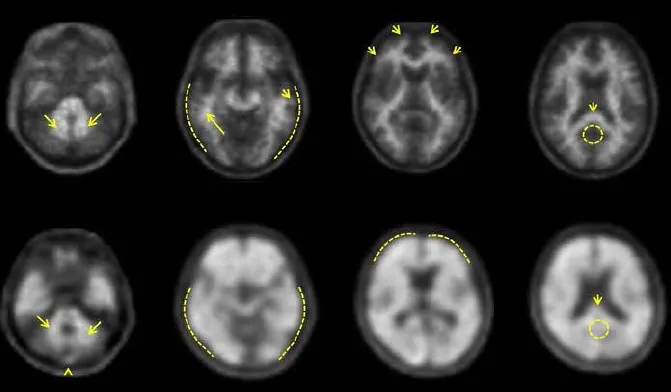

NeuraCeq™ est un agent de diagnostic radioactif indiqué pour l’imagerie par tomographie par émission de positons (TEP) du cerveau afin d’estimer la densité des plaques névritiques β-amyloïdes chez les patients adultes atteints de troubles cognitifs qui sont évalués pour la maladie d’Alzheimer (MA) et d’autres causes de déclin cognitif.